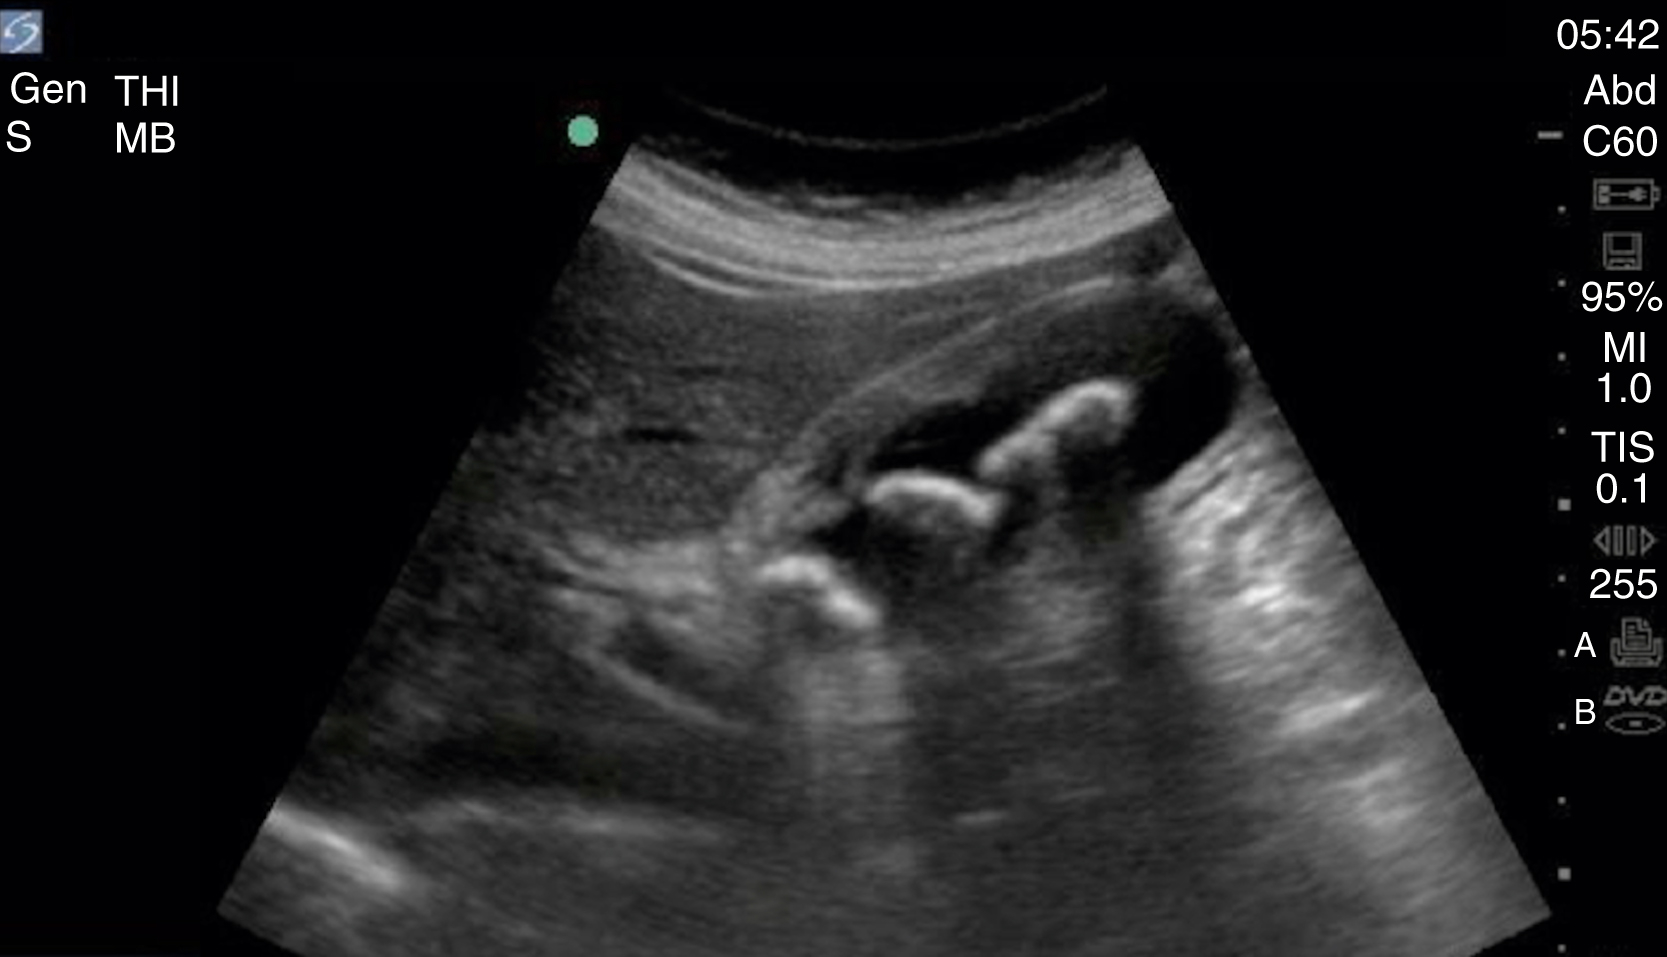

The FAST examination technique uses a low-frequency broadband transducer (2–6 MHz) to evaluate dependent peritoneal spaces, pleural spaces, and the pericardium for free fluid, which in the trauma patient is presumed to be blood. There are four main components of the basic FAST examination: (1) the right upper quadrant (RUQ) view, (2) the left upper quadrant (LUQ) view, (3) the pelvic view and (4) the cardiac view ( Fig. e3.1 ). The E-FAST includes anterior chest views to evaluate for pneumothorax. The RUQ view evaluates for fluid in the thorax (above the diaphragm) ( Video e3.1 ), hepatorenal space (Morison pouch) and the paracolic gutter (inferior edge of the liver and right kidney) ( Video e3.2 ), moving cephalad to caudad. The LUQ view, found slightly more superior and posterior than the RUQ, should mimic the RUQ views, but also include the subdiaphragmatic space, because free intraperitoneal fluid tends to accumulate here initially. The pelvis should be evaluated in the transverse and longitudinal planes, where fluid may be detected deep to the uterus (in females) or in the retrovesical space (in males) ( Video e3.3 ). The cardiac evaluation can be performed in either the subcostal (or subxiphoid) or parasternal window ( Video e3.4 ). Evaluation for pneumothorax uses a low or high-frequency transducer at a shallow depth, placed along the anterior chest wall and will be discussed in more detail in subsequent sections.

Fig. e3.1

Negative FAST images. (A) Subxiphoid view with no pericardial effusion. (B) Negative RUQ view showing the thorax and hepatorenal space without the paracolic gutter visualized. There is mirroring and loss of the spine, indicating a negative thorax. (C) Negative paracolic gutter area by the liver tip in the RUQ view. (D) LUQ view showing negative thorax, as in B, and splenorenal space. (E) Negative transverse bladder view. (F) Negative sagittal bladder view.